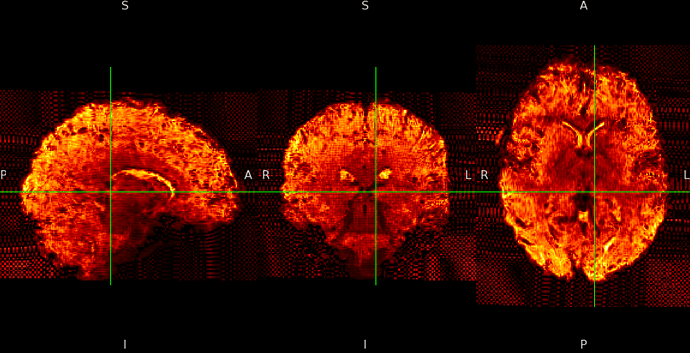

ME sequence in MNI152NLin6Asym-res1

The checkerboard pattern is more evident in the ME sequence where it is also visible outside the brain, but it is present in both, ME and SE inside the brain.